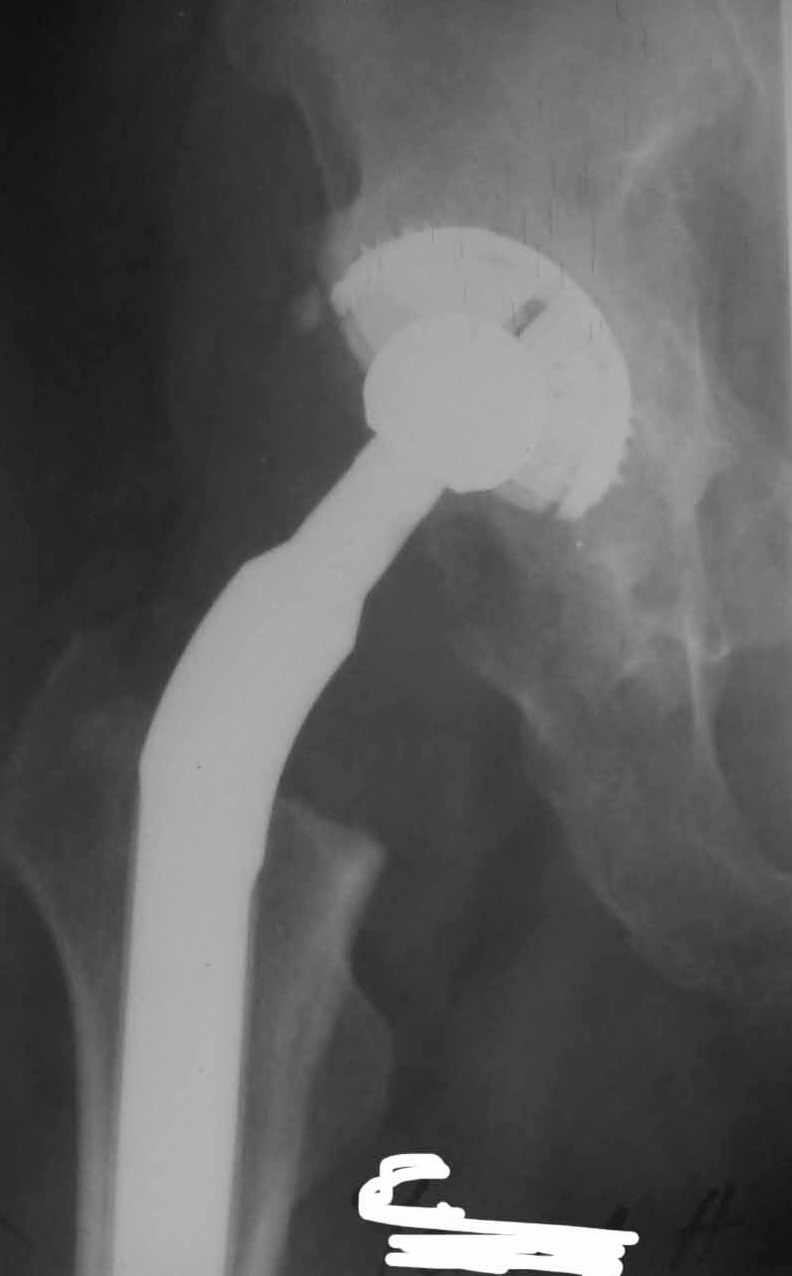

Сан Саныч,

Консультировать вывихи по рентгенограммам, не зная хода операции, дело не очень благодарное. Я думаю, что с датой операции Вы ошиблись и это был 2004 год? Тем не менее. Настораживают два фактора. Первое - не видно большого вертела. Если с мышцами обошлись грубо и их отсекли, то это очень грустно и нужна "связанная" пара, т.н. "constrain cup". Смущает хорошо прослеживаемый малый вертел и небольшая ретроверсия чашки. Возможно это (избыточная ретроверсия ножки и чашки) могло послужить причиной вывиха. Обычно гипсовая повязка после операции не накладывается, значит, были глубокие сомнения у оперировавшего хирурга. В этом случае - ревизия с перестановкой как минимум - ножки, а как максимум - обоих компонентов.

Но желательно бы знать ход операции.

Во вложении - рентгенограммы после вывиха и после вправления.